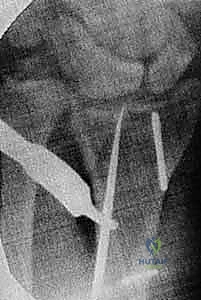

** Intra-articular Distal Radius Osteotomy **Intra-articular osteotomy should be attempted only when there is a simple fracture line that can be clearly identified by direct visualization as well as under image intensification ( TECH FIG 6A-C). Incompletely healed fractures (fewer than 3 to 4 months since injury) are ideal. Depending on the locations of the malunited articular fragments, perform either a dorsal or a volar exposure in the manner detailed earlier. When a dorsal exposure is used, a transverse capsulotomy allows access to the joint and monitoring of the articular osteotomy and realignment. In the case of a volar exposure, the capsule is not incised, but articular exposure may be possible through the osteotomy site. The osteotomy should recreate the original fracture line. This is monitored directly and under image intensification. Reduction is accomplished by soft tissue release and direct fragment manipulation. For many malunions, it is necessary to remove bone or callus from the fracture site to realign the fracture fragment. Callus or bone is removed until the fracture fragment fits properly ( TECH FIG 6D). Provisional Kirschner wires are used to hold the reduction ( TECH FIG 6E,F). The implants are then applied. Dorsally, a single T- or Pi-shaped plate or two 2.0- or 2.4-mm plates (one applied dorsally, ulnar to the tubercle of Lister, and the other applied radially between the first and second dorsal compartments) can be used ( TECH FIG 6G,H). Volarly, a T-shaped plate is usually used. After final plate fixation, provisional fixation is removed. This entire process is monitored using image intensification to confirm appropriate osteotomy site, correction of alignment, and implant placement. Deflate the tourniquet, close the wound, and apply the splint in the manner detailed earlier. 150

### TECH FIG 6 • A-C. PA and lateral radiographs and CT of an intra-articular dorsally angulated malunion. D. A Freer elevator is used under fluoroscopy to reposition the articular fragment. E,F. Intraoperative fluoroscopic views showing provisional correction and fixation. G,H. Final plate and screw fixation. (Copyright Diego Fernandez, MD, PhD.)